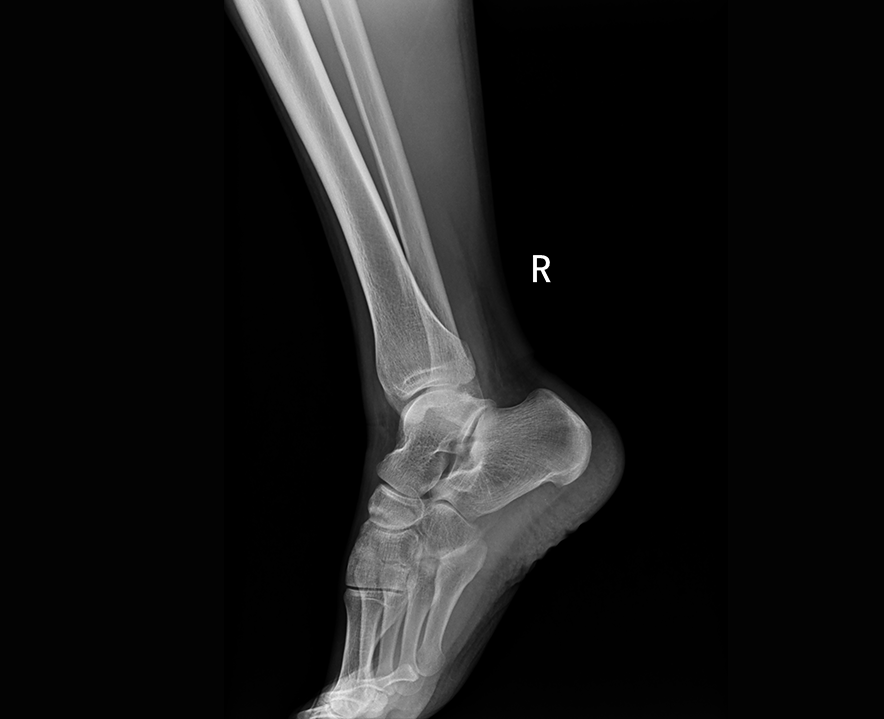

临床图像